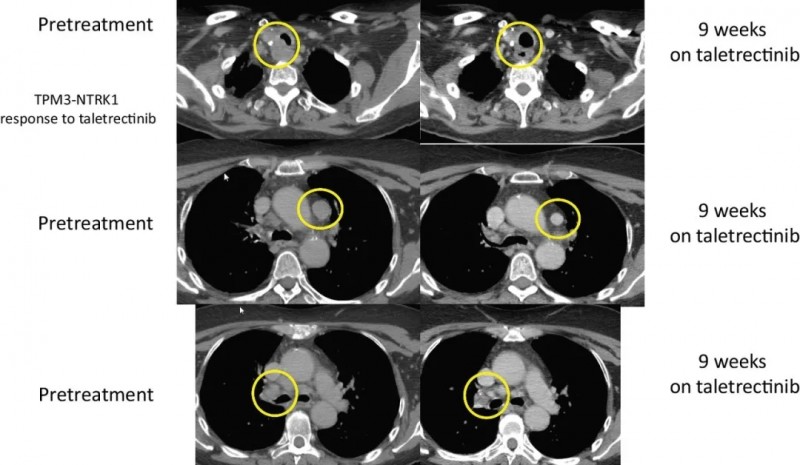

甲状腺癌:

另一位患者是晚期甲状腺癌,手术后接受了化学放疗,放射性I-131,索拉非尼,以及PD-1的临床试验,后经过FoundationOneCDx检测到存在TPM3-NTRK1融合,参加了taletrectinib的临床试验,截止到文献发表,这名幸运的患者持续缓解时间已经长达33.4个月,将近3年。